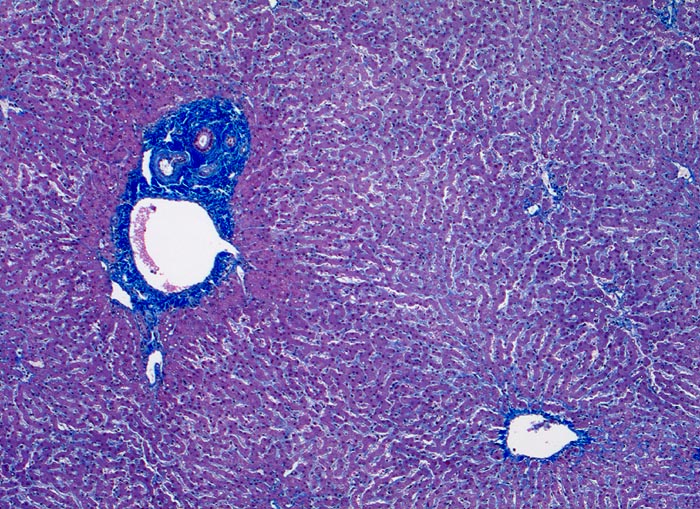

Bei ausgeprägten Eisenablagerungen zeigen parenchymatöse Organe eine Braunverfärbung (> 1521). Die Bestimmung des histologischen hepatischen Eisenindexes nach Deugnier erlaubt eine Abgrenzung der genetisch bedingten Hämochromatose von einer Hämosiderose. Dabei werden Verteilung und Ausmass der Eisenablagerungen berücksichtigt. Bei der Hämochromatose wird das Eisen primär in den periportalen Hepatozyten abgelagert, später auch in Gallengangsepithelien und Gefässendothelien. Bei nicht genetisch bedingter Hämosiderose finden sich die Ablagerungen vor allem in Kupffer Zellen (> 00975).

• Erhaltene Läppchenarchitektur.

• Diffuse grobgranuläre Eisenpigmentablagerungen im Zytoplasma von Hepatozyten, Gallengangsepithel und Gefässendothel der Gefässe in den Portalfeldern.

• Gruppen von stark eisenbeladenen Kupffer'schen Sternzellen. Das sollte der Kliniker dem Pathologen mitteilen: